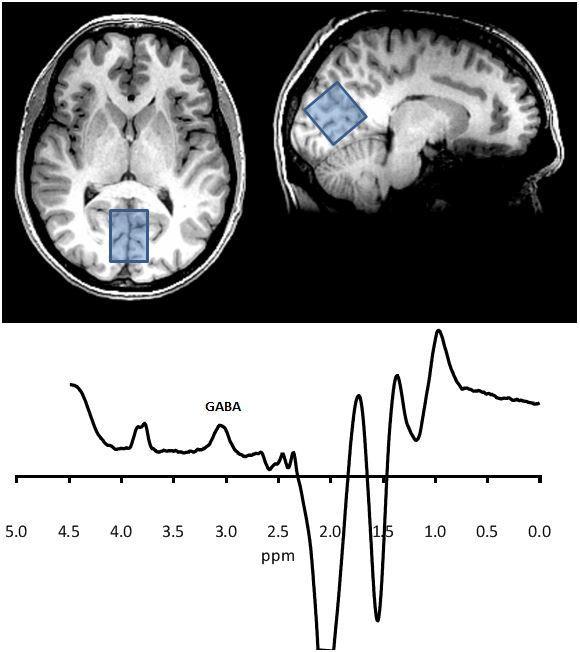

Fig. 3

An MRS recording - peaks give a measure of the concentration of different substances

This fig shows a spectrum analysed in such a way as to enhance the signal from the specific resonances in the GABA molecule. The area under the GABA peak represents its concentration in the large occipital voxel shown. Other peaks can be defined that represent other molecules such as glutamate, creatinine, choline and N-acetylaspartate.

MRS = magnetic resonance spectroscopy – is used to measure biochemical changes in the brain.

MRS is used to measure the concentrations of certain biological molecules in the brain. The atoms within these molecules resonate at specific frequencies according to the specific bonds between them, so each has its own fingerprint within a larger spectrum. Higher magnetic field strengths improve the resolution of the spectrum, but overlap of the signals of various molecules usually means scanning a large voxel (approx 25 cc) for about 10 mins.

Here we can measure levels of certain metabolic substances such as NAA (n-acetylaspartate) and creatinine and glutamate/glutamine. At high magnet strengths, e.g. 3 Tesla and above then other substances such as GABA can be measured, Fig 3.

Currently the clinical applications of MRS are limited but it is used to explore changes in metabolic pathways e.g. in dementias and in some genetic disorders. Alterations in brain glutamate have been detected after some drug treatments e.g. with the glutamate receptor blocker ketamine.